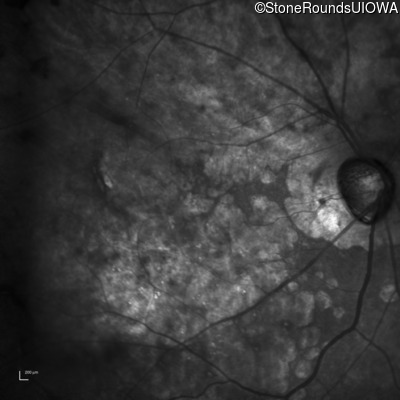

This 81 year old man began using a flashlight to read menus in his 40's. At age 75 his ophthalmologist noticed abnormal fundus findings and referred him to a retina specialist.

Diagnosis & molecular findings

| Disease | Gene | Allele 1 variant(s) | Allele 2 variant(s) | Inheritance mode |

|---|---|---|---|---|

| Late Onset Retinal Dystrophy | C1QTNF5 | Ser163Arg AGC>AGA | AD |

Disease:

Gene:

Allele 1:

Ser163Arg AGC>AGA

Allele 2:

Inheritance:

AD